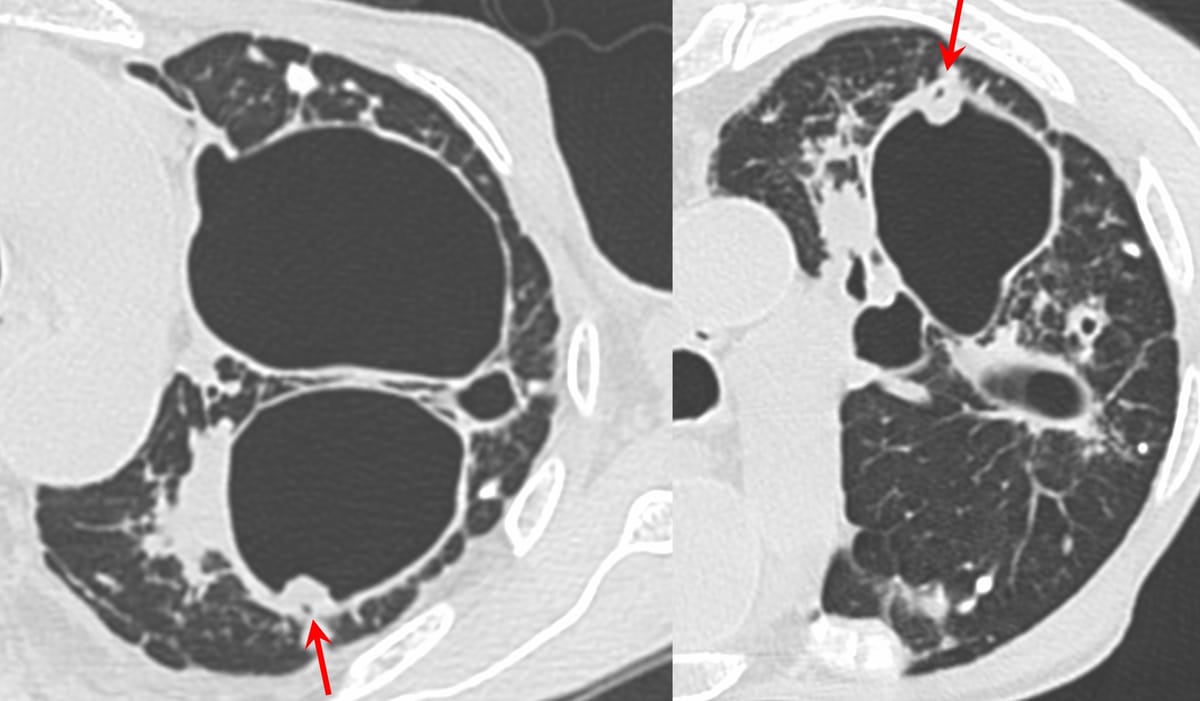

The "scab-like" sign helps pick up early CPA/CCPA

429-years old with PTLD had fever and weight loss. CT in July 2025 showed a "scab-like" sign, suggesting chronic pulmonary aspergillosis (CPA). This was also discussed in Case of the Day 16 and in Case 20

Case 20: “Scab-Like” Sign for Chronic Cavitary Aspergillosis

Post-tuberculous cavities with the “scab-like” sign predicting chronic cavitary pulmonary aspergillosis